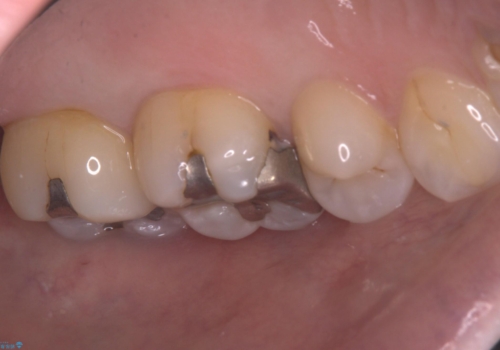

適合性・審美性を考慮し、セラミックインレーでのやり替えとなりました。